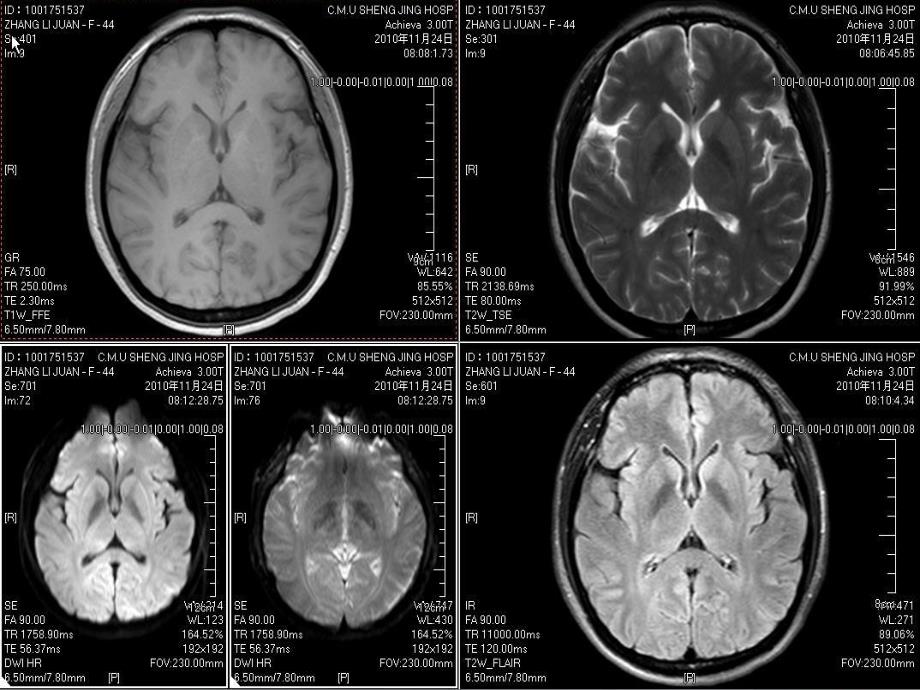

1、头部磁共振常用序列临床应用简介23头部MR相关成像技术n自旋回波序列:SE(spin echo)、FSEn反转恢复序列(inversion recovery,IR):STIR、FLAIRn梯度回波序列(gradient recall echo,GRE)4 CNS相关的成像技术n自旋回波(SE)和快速自旋回波(FSE)序列(1)SE序列目前多用于获取T1WI,是颅脑、脊柱 和脊髓等部位常规T1WI序列 SE序列优点 影像具有良好信噪比、组织对比良好 对磁场不均匀敏感性低,无明显磁化率伪影 T1WI采集时间一般仅为25min5 CNS相关的成像技术n反转恢复(IR)序列(1)IR序列T1对比最佳,

4、于超急性期缺血性脑梗死的诊断和鉴别诊断该期脑梗死主要引起细胞毒性水肿,与常规T1WI 和T2WI相比,DWI能更早发现梗死区信号异常,可提早到病后2小时之内10CNS相关的成像技术nMR扩散加权成像(3)DWI的临床应用、影像学表现超急性/急性期缺血性脑梗死表现为高信号MS的活动病灶、部分肿瘤、血肿及脓肿等也可能表现为高信号利用DTI技术进行脑白质束成像,显示肿瘤对周围白质束的影响11DTI显示双侧放射冠及胼胝体的纤维走行DTI孤立病灶孤立病灶孤立病灶DTI显示局部纤维中断12常规头部常规头部MR序列序列nT1W-T1W-信噪比高,灰白质对比强,对解剖结构的显信噪比高,灰白质对比强,对解剖结构

5、的显示好示好nT2W FSET2W FSE(TSETSE)-常规常规T2T2像像,用于一般病变的检出用于一般病变的检出,如梗塞灶、肿瘤等,如梗塞灶、肿瘤等nT2W FlairT2W Flair水抑制技术,显示被水抑制技术,显示被CSFCSF高信号掩盖高信号掩盖的的脑和脊髓的脑和脊髓的稍高或高信号病稍高或高信号病nDWI-EPI-DWI-EPI-是目前惟一能检测活体组织内水分子是目前惟一能检测活体组织内水分子扩散运动的无创性方法。扩散运动的无创性方法。b b值值(扩散敏感梯度场参扩散敏感梯度场参数数)一般选择一般选择1000 s/mm1000 s/mm2 2。主要用于超急性期缺主要用于超急性期缺